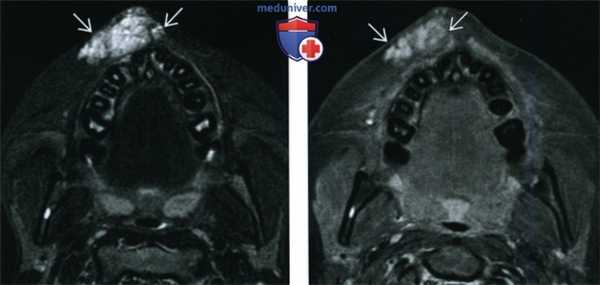

(Слева) При аксиальной МРТ STIR в подкожных тканях в области верхней губы определяется венозная мальформация в виде объемного образования с бугристыми краями, хорошо отграниченного от окружающих тканей. Патологические изменения со стороны костей и зубов отсутствуют.

(Справа) При аксиальной МРТ Т1ВИ С+ FS y этого же пациента визуализируются патологически расширенные венозные сосуды, умеренно и неравномерно накапливающие контраст.